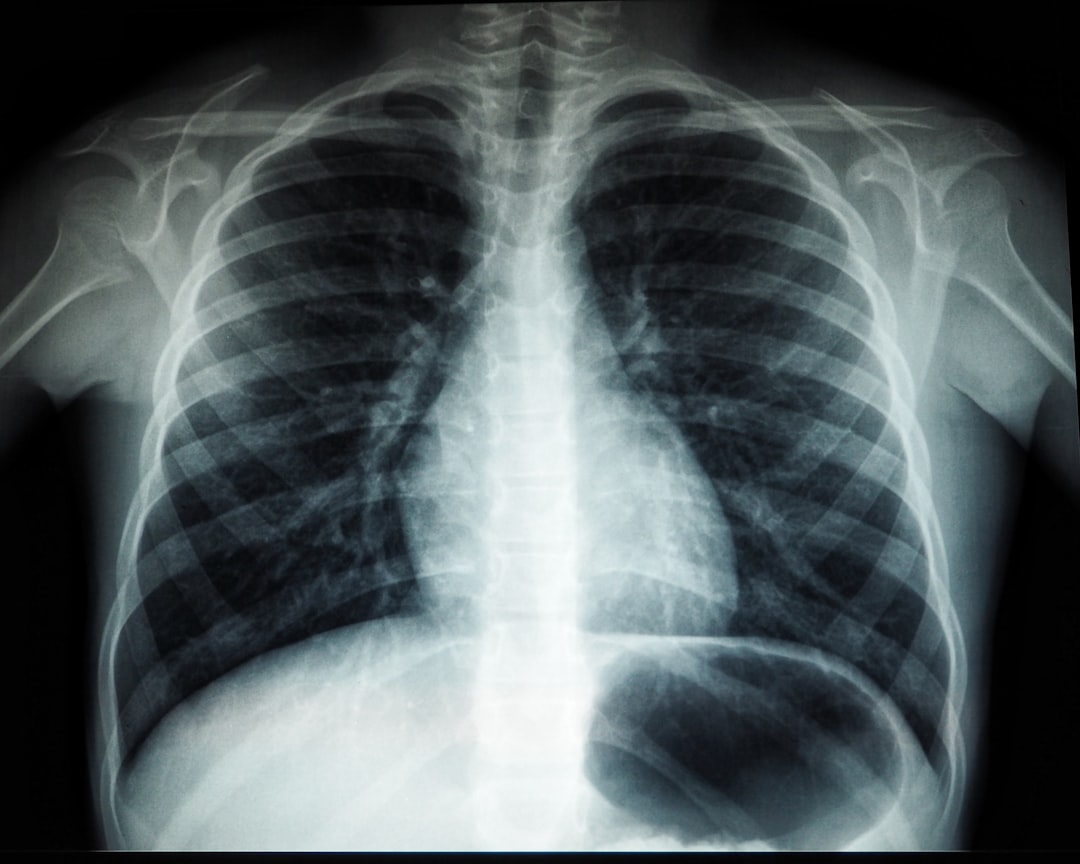

보건소 잠복결핵검사는 잠복 결핵 감염 여부를 확인하는 검사입니다. 잠복 결핵은 우리 몸의 면역 시스템이 결핵균을 죽이지는 못하지만, 활성화도 되지 않은 상태입니다. 이런 경우 증상이 없으므로 검사 없이는 알기 어렵습니다. 따라서 보건소에서 제공하는 잠복결핵검사는 매우 중요합니다.

각 보건소마다 다를 수 있지만, 검사 방법은 대개 두 가지로 나뉩니다. 하나는 피부 검사, 다른 하나는 혈액 검사입니다. 보건소 잠복결핵검사를 통해, 나는 제 자신이 결핵에 감염됐는지 알 수 있게 되어 안도감을 느꼈습니다.